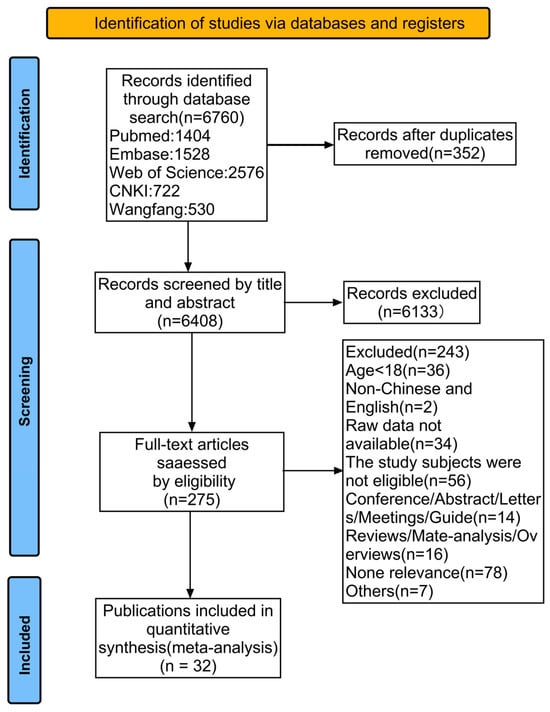

Open AccessSystematic Review

Incidence and Risk Factors of Platinum-Based Chemotherapy-Induced Nausea and Vomiting: A Systematic Review and Meta-Analysis

by

Kaili Jin, Xianlei Lin, Xiaoting Xia, Huiling Ye, Dan Yang, Ying Fan, Qiuhua Sun and Rongyun Wang

Curr. Oncol. 2025, 32(6), 325; https://doi.org/10.3390/curroncol32060325 - 31 May 2025

Background: Platinum-based chemotherapy significantly increases the risk of nausea and vomiting, which can impair the treatment’s efficacy and the patient’s quality of life. This meta-analysis examines the incidence and risk factors of platinum-based chemotherapy-induced nausea and vomiting (PINV) in patients treated with this

Background: Platinum-based chemotherapy significantly increases the risk of nausea and vomiting, which can impair the treatment’s efficacy and the patient’s quality of life. This meta-analysis examines the incidence and risk factors of platinum-based chemotherapy-induced nausea and vomiting (PINV) in patients treated with this chemotherapy. Methods: This systematic review and meta-analysis were conducted in accordance with the PRISMA 2020 guidelines. We conducted a literature search in the databases PubMed, Embase, Web of Science, WanFang, China Science and Technology Journal Database (VIP), China National Knowledge Infrastructure (CNKI), and Chinese Medical Association Journal Database (CMAJD) through to 20 January 2025. Studies that reported the incidence and identified risk factors of nausea and vomiting specifically in patients receiving platinum-based chemotherapy were included in the review. The data were extracted independently by two reviewers. The odds ratios (ORs) for each risk factor were calculated from the included studies. Sensitivity analyses and additional subgroup analyses were performed to ensure the robustness of our findings. Results: This meta-analysis included 32 studies involving 14,207 participants. Female sex (OR = 2.363, 95% CI = 1.363–4.096, p = 0.002), anxiety (OR = 1.689, 95% CI = 1.057–2.700, p = 0.028), fatigue (OR = 1.413, 95% CI = 1.145–1.744, p = 0.001), motion sickness (OR = 1.816, 95% CI = 1.266–2.605, p = 0.001), and a history of vomiting during chemotherapy (OR = 2.728, 95% CI = 1.468–5.069, p = 0.002) were significantly associated with an increased risk of PINV. Conclusion: Female sex, anxiety, fatigue, motion sickness, and a history of vomiting during chemotherapy increase the risk of PINV during platinum-based treatments.

(This article belongs to the Section Palliative and Supportive Care)

Figure 1